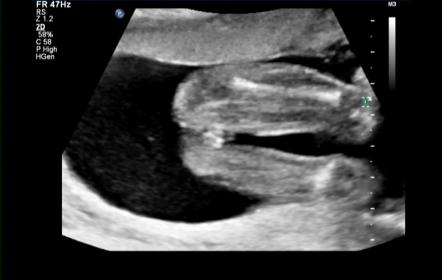

Hello lovely ladies :) Soooooo had my 20 week anatomy scan this morning and as you all guessed it right bubs is a :ballerina: We're over the moon that she is healthy!! The tech took a nub shot to confirm gender though which I thought was a little odd as Im so used to seeing potty shots so Ive snapped a few off my dvd and included her nub shot but just hoping to get your confirmation too please xx